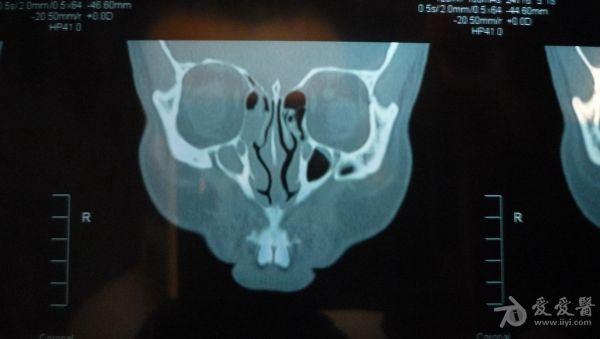

CT结果是右侧上颌窦及部分筛窦窦腔内见稍高密度影填充,CT值约21U,窦壁骨质未见破坏征象;鼻腔后部亦见少量稍高密度影填充;左侧上颌窦、筛窦及蝶窦、额窦未见明显异常。CT图片见附件。医生说我的右边鼻窦都被软组织堵死了,必须要做手术清楚后再做病理分析看是良性还是恶性。

想请问下医生:CT图片上右边的上颌窦内的稍高密度影,是软组织还是液体的几率大些呢